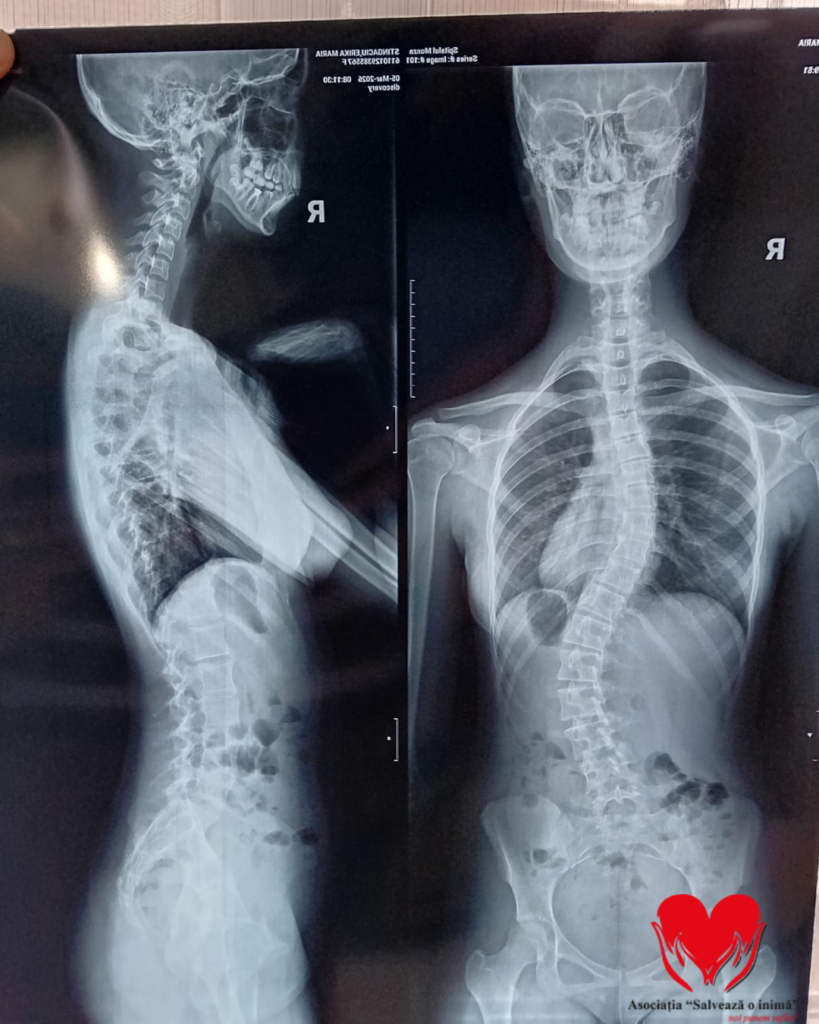

O adolescentă de doar 15 ani din Râmnicu Vâlcea luptă cu o afecțiune gravă care îi afectează viața de zi cu zi. Erika Maria Stîngaciu a fost diagnosticată cu scolioză dorsolombară progresivă, o boală care îi modifică postura și îi provoacă dureri constante.

Povestea ei a început în februarie 2024, când un consult medical de rutină a scos la iveală o problemă aparent minoră. În urma investigațiilor, medicii au confirmat diagnosticul de scolioză idiopatică lombară.

De atunci, Erika a urmat zilnic ședințe de kinetoterapie și a fost nevoită să poarte un corset rigid tip Cheneau aproape permanent, 23 de ore din 24. Cu toate acestea, evoluția bolii nu a putut fi oprită.

În februarie 2026, medicii au confirmat agravarea afecțiunii și necesitatea unei intervenții chirurgicale.